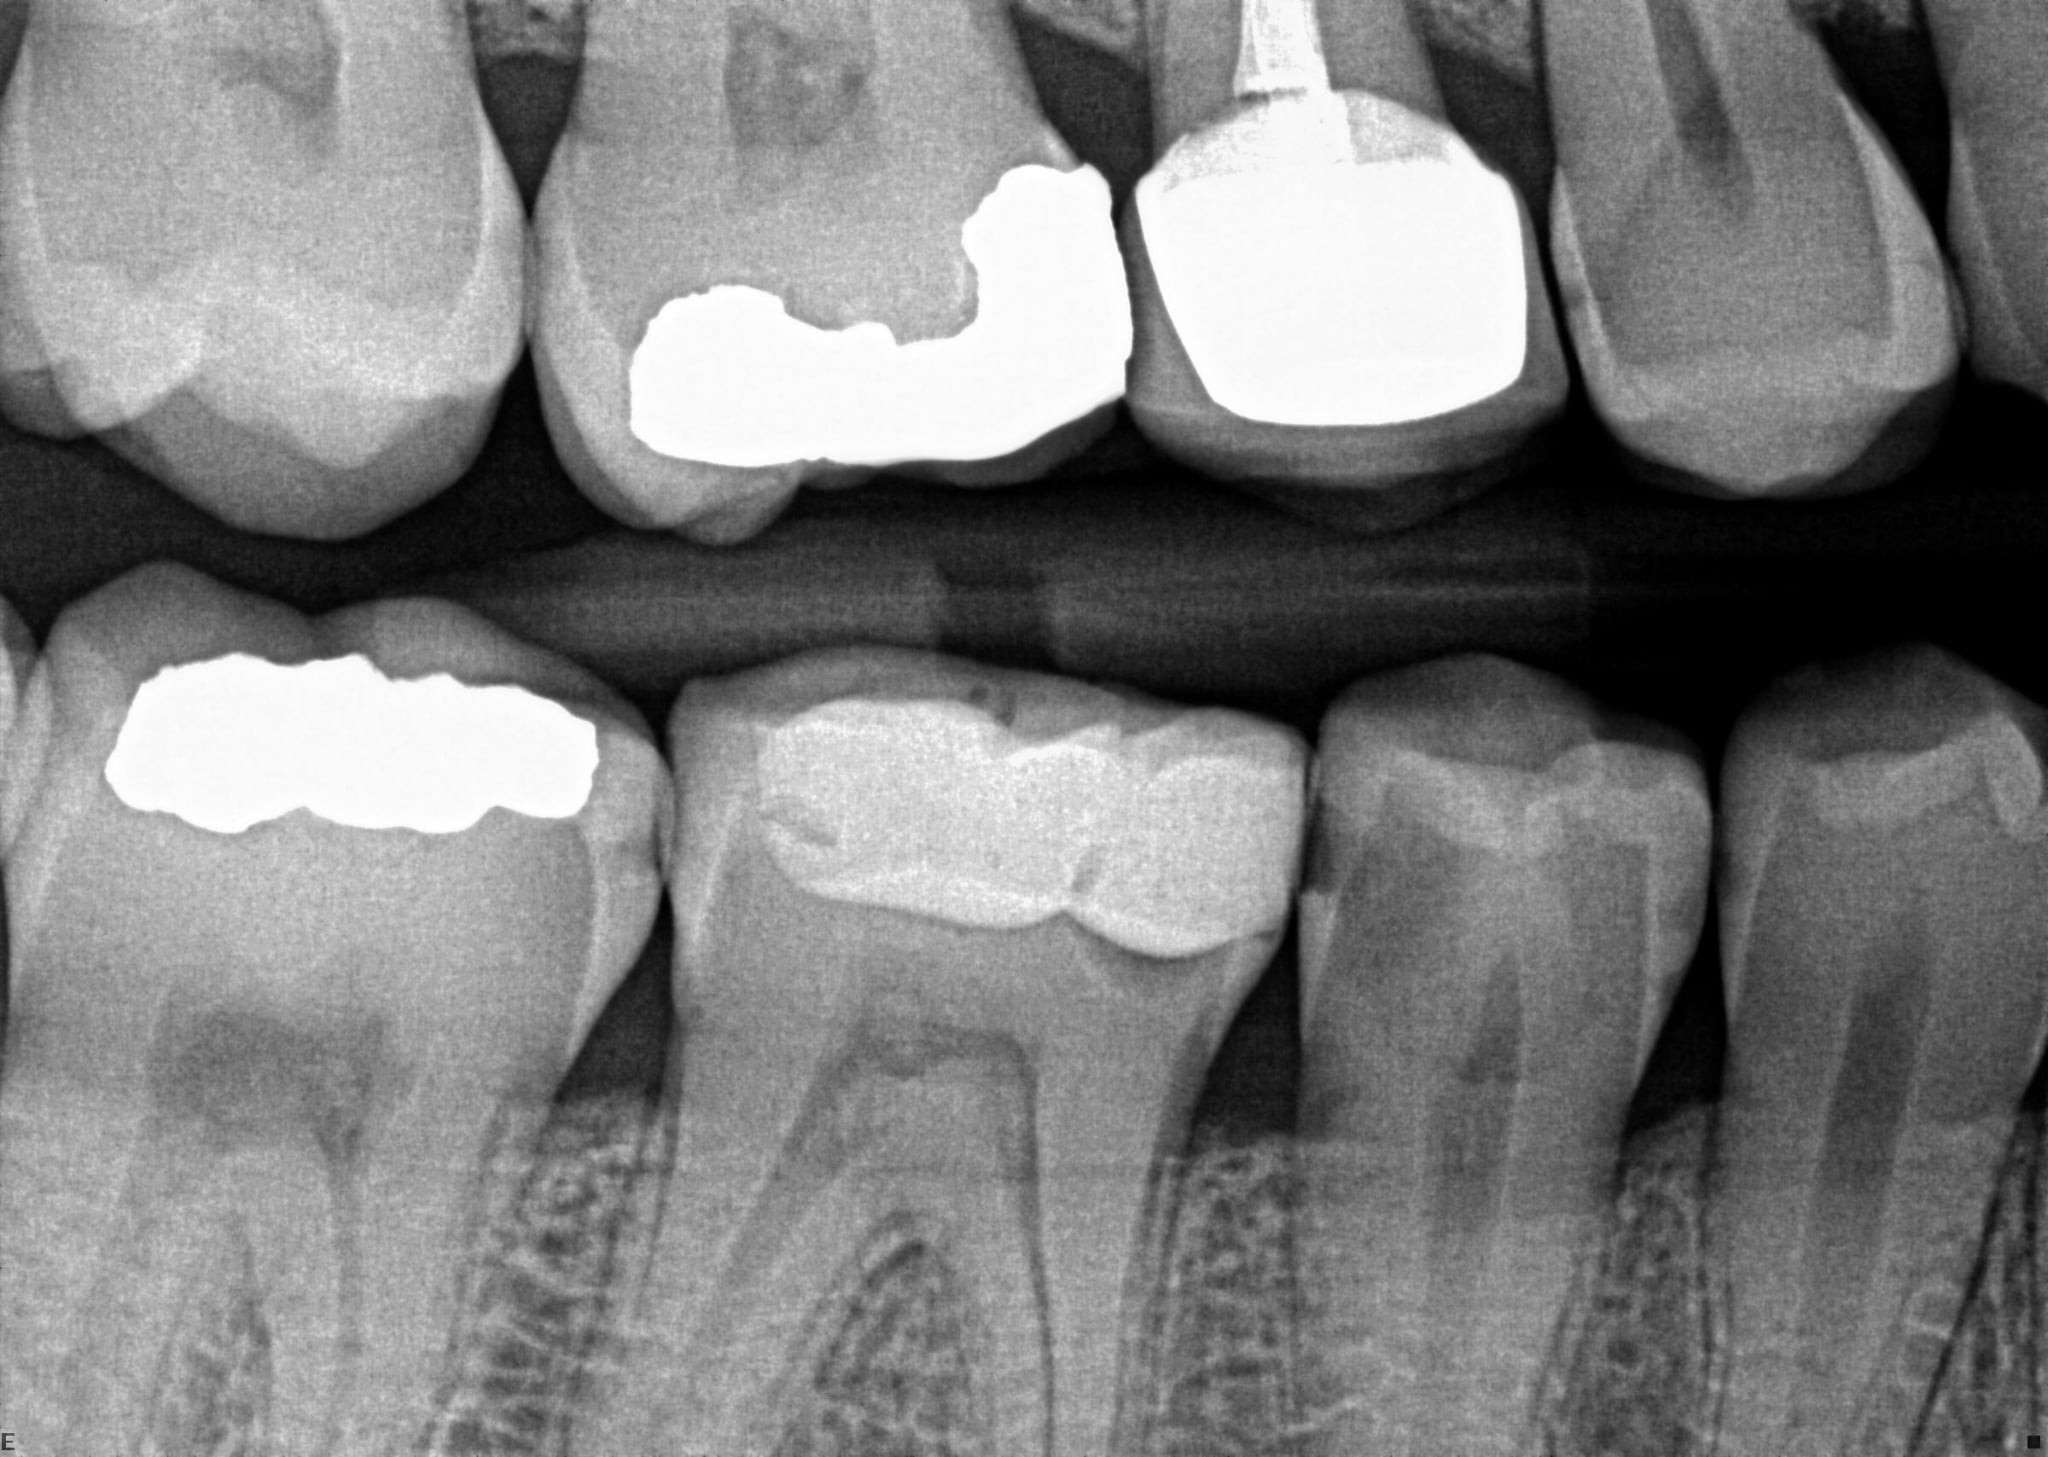

11. On which surface a recurrent caries can be detected?

12 / 35

12. On which surface a recurrent caries can be detected?

Mesial 4.7 is normal proximal caries not recurrent, distal 4.6 is recurrent , mesial 4.6 and distal 4.5 are open margin